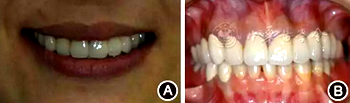

全口根尖X線片示鄰面骨嵴頂影像模糊;根管欠填、根充不致密,、未見根管治療影像,、根尖周可見低密度影像(圖2)。

圖2 患者初診時全口根尖X線片